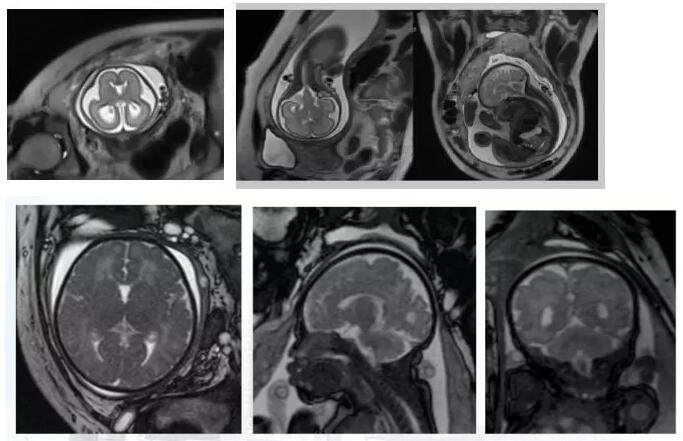

磁共振檢查不受胎兒骨骼及羊水量的影響,對胎兒中樞神經(jīng)系統(tǒng)、羊水過少、雙胎、孕周較大時顯示很好,特別是孕晚期胎頭入盆或胎兒顱骨骨化時。

磁共振圖像可以在各個方位看到寶寶的顱腦,還能看到寶寶撅起的小嘴。

磁共振圖像可以在各個方位看到寶寶的顱腦